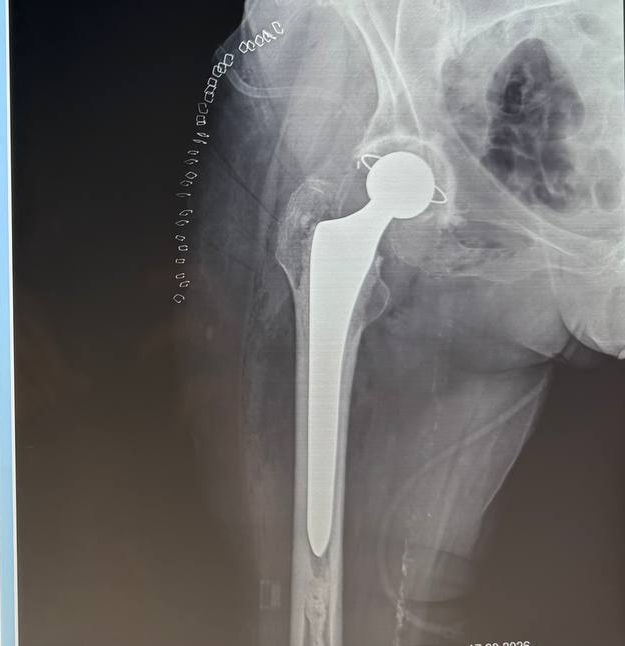

У травматологічному відділенні нашої лікарні проводяться операції з ендопротезування кульшового суглоба в межах державної програми МОЗ України. Завдяки сучасним методикам і досвіду лікарів пацієнти отримують можливість позбутися болю та повернутися до активного життя.

Нещодавно в лікарні було проведено ендопротезування жінці 80 років. Операція пройшла успішно — пацієнтка почувається добре та вже розпочинає етап реабілітації. 💙